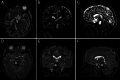

Observations: Here, the authors present the case of a 3-year-old male who presented with hemiparesis and eventually developed hydrocephalus from a giant brainstem cavernous malformation. The patient initially did well on steroids but had a recurrent hemorrhage that led to worsening hemiparesis and hydrocephalus. The authors then elected to resect the cavernous malformation via a supracerebellar infratentorial approach utilizing intraoperative MRI to ensure complete resection. Postoperatively, the patient returned to near baseline neurological function.